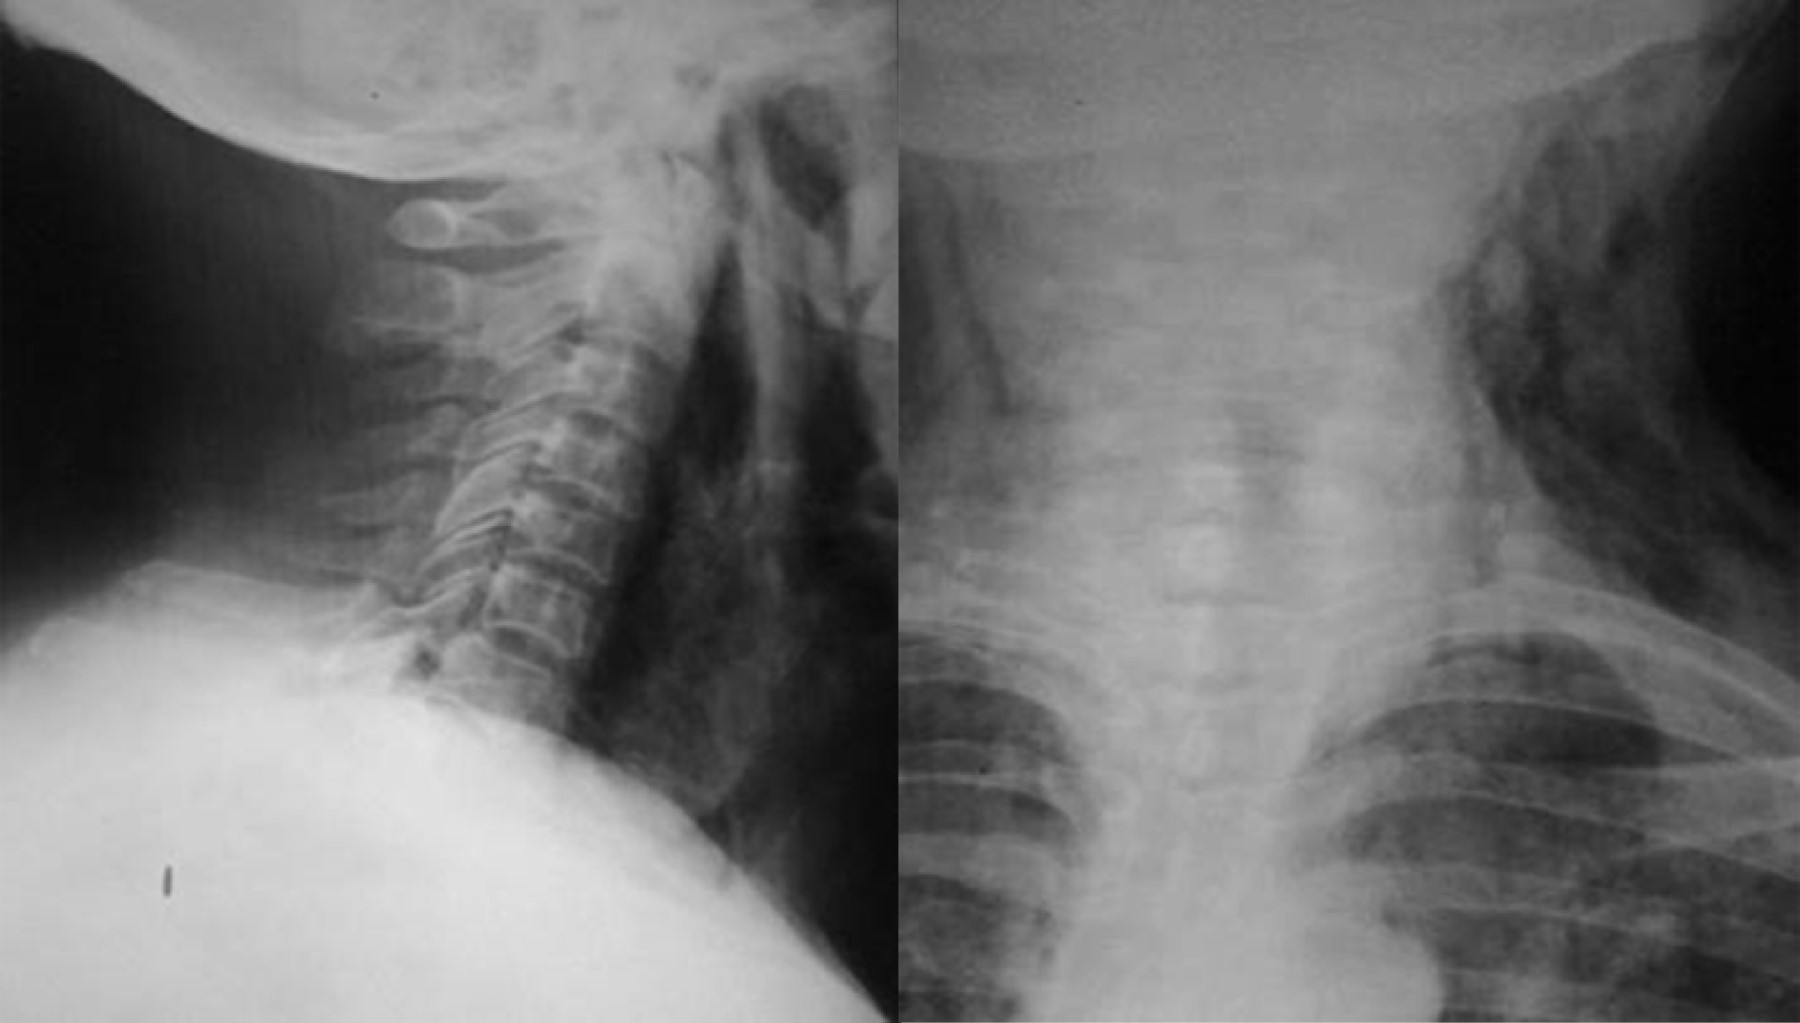

Se realizaron en total 18 procedimientos, se consideró como complicación sólo un paciente (7.1%), quien presentó sangrado importante, mismo que se controló, pero impidió en el procedimiento inicial completar adecuadamente la miotomía, por lo que se reintervino a las 24 horas para completar ésta. Durante los procedimientos, dos pacientes tuvieron enfisema subcutáneo (un paciente femenino de 74 años y uno masculino de 57 años), los cuales fueron tratados de forma conservadora mediante la administración de una cefalosporina de tercera generación, así como control radiográfico para medición del enfisema subcutáneo (Figura 6). No se presentaron complicaciones mayores como mediastinitis, hemorragia incoercible o perforación que requirieran cambiar el tratamiento endoscópico por el quirúrgico de urgencia o programado. La mejoría de la disfagia en todos los casos fue inmediata y en las consultas subsecuentes refirieron haber aumentado de peso, además se realizó endoscopia y trago de material de control (Figura 7).

Figura 6